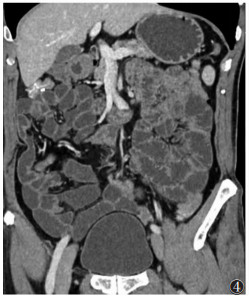

小肠CT造影所用的对比剂分为阴性对比剂和阳性对比剂,阴性对比剂有水、0.5%~1%的甲基纤维素溶液、2.5%的等渗甘露醇溶液等,阳性对比剂有低浓度碘剂溶液(浓度2%~3%)和钡剂混悬液(浓度0.001 kg/L)。肠道内使用阴性对比剂结合血管内对比增强应用较多。对比剂用量一般1 500~2 000 mL,30~45 min内每隔15 min分次口服或经导管引入,导管引入流率75~150 mL/min,检查前肌内注射山莨菪碱针剂20 mg(前列腺肥大、青光眼、心律不齐者禁用)。口服法较导管法易于患者接受,且有研究[6-7]表明两者图像效果差异不显著(图 4)。

![]() |

| 图 4 小肠CT造影MPR冠状位重组图像(口服甘露醇),小肠肠腔充盈良好,小肠壁显示清晰 |